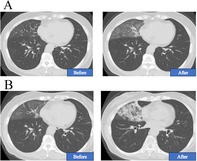

一位70岁的女性患者被诊断为IV期egfr突变型非小细胞肺癌,在接受化疗时经历了三种不同的外源性脂质肺炎。胸部CT一致显示毛玻璃混浊,呈疯狂铺路状,支气管镜检查证实脂质,cd163阳性泡沫巨噬细胞的存在。值得注意的是,每次发作都与不同的外源性暴露有关:鼻内施用凡士林,长时间使用煤油加热器,随后鼻内使用骏马润肤油。所有的发作都发生在右中叶,并在停止发作剂后得到解决。这是首例由多种不相关物质引起的单一患者复发性外源性脂质性肺炎的报道。该病例强调了放射学模式的诊断价值,细致的暴露史的重要性,以及在癌症治疗期间考虑新浸润患者的其他病因的必要性。

A 70-year-old female patient diagnosed with stage IV EGFR-mutant non-small-cell lung cancer experienced three distinct instances of exogenous lipoid pneumonia while undergoing chemotherapy. Chest CT consistently revealed ground-glass opacities with a crazy-paving pattern, and bronchoscopy confirmed the presence of lipid-laden, CD163-positive foamy macrophages. It is noteworthy that each episode was associated with a distinct exogenous exposure: intranasal administration of petroleum jelly, prolonged utilisation of a kerosene heater, and subsequently, intranasal application of Junma Moisturising Oil. The localisation of all episodes to the right middle lobe was noted, and resolution was attained with the cessation of the offending agent. This is the first reported case of recurrent exogenous lipoid pneumonia in a single patient caused by multiple unrelated substances. This case underscores the diagnostic value of radiologic patterns, the significance of meticulous exposure history, and the necessity of contemplating alternative aetiologies in patients with new infiltrates during cancer therapy.